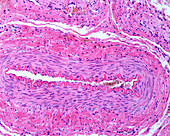

13613516 - Vein adventitia, light micrograph

13613519 - Layers of a large vein wall, light micrograph

13613518 - Layers of a large vein wall, light micrograph

13613504 - Muscular artery, light micrograph